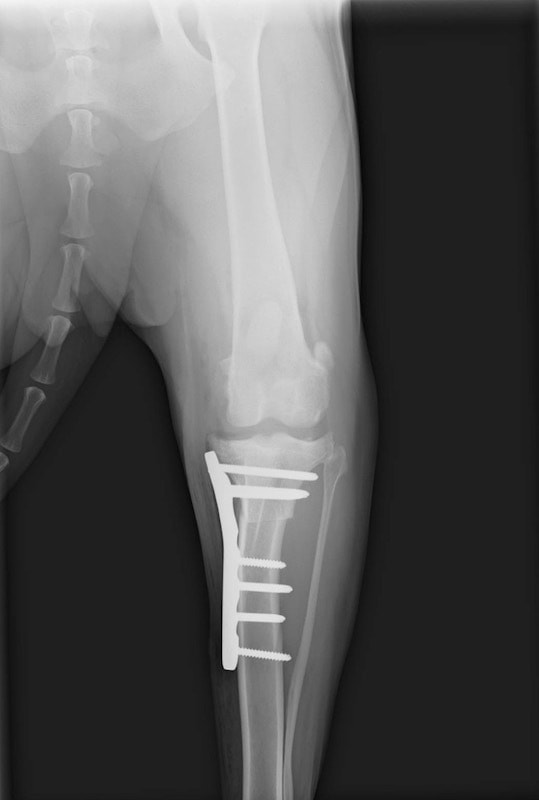

術後左後肢側面像

術後側面像

・術後レントゲン

手術前TPA 28.4° が術後TPA 11.7° に矯正されました。